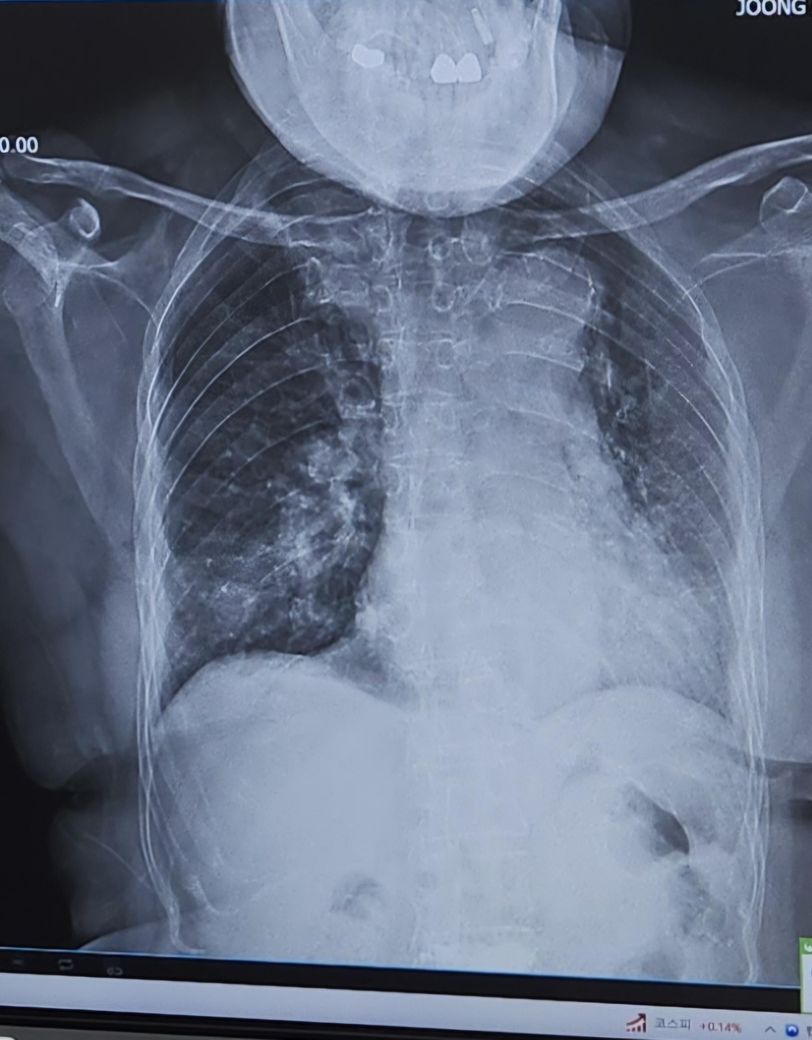

일주일전 찍은사진과 일주일후사진입니다.

궁금합니다. 위사진이 일주전 아래가 일주후 입니다

엑스레이로는 좋아진걸로 보이진 않습니다

우선 폐렴의 엑스레이 소견과 임상 증상(기침, 가래, 호흡곤란 등)은 반드시 일치하지 않을 수 있습니다. 환자의 증상이 호전되었더라도 엑스레이에서는 염증이 여전히 남아 있거나 심하게 보일 수도 있습니다. 이는 폐 조직의 회복 속도가 느리기 때문이며, 폐렴이 회복되는 과정에서도 폐 조직 내에 염증 흔적이 남아 있을 수 있습니다. 반대로, 엑스레이에서 크게 변화가 없어 보여도 환자의 증상이 뚜렷이 호전될 수도 있습니다.

이래서 엑스레이만으로 폐렴 상태를 정확하게 판단 할 수 없다는 거에요